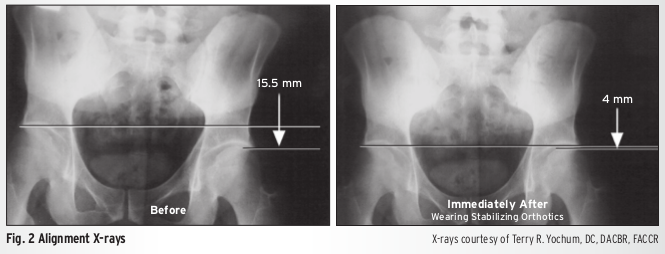

In fact, one study shows that 4 months of orthotic usage resulted in improvement in 3 key measurables:

- Femoral head height (5mm average improvement) (Fig. 2)